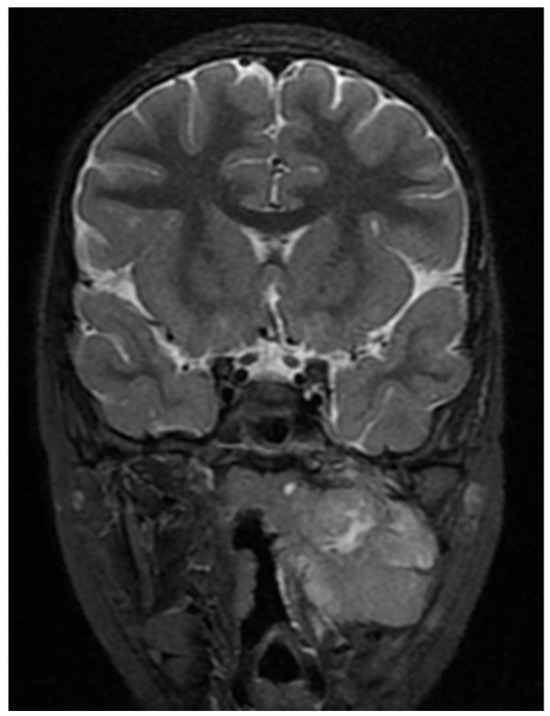

The restating MRI before the fourth chemotherapeutic block showed persisting tumor mass in the nasopharynx and oropharynx with reduced size in the different dimensions 15/44 mm axial size and 31/40 mm coronal size. The lesion involves the vascular nerve bundle in the area of the cavernous sinus. In the skull base area, the formation was closely adjacent to the internal carotid artery. Full morphologic response to the cervical lymph nodes. (Figure 9, Figure 10 and Figure 11).

Figure 9. MRI on the 4th month from the start of chemotherapy.

Figure 10. MRI on the 4th month from the start of chemotherapy.

Figure 11. MRI on the 4th month from the start of chemotherapy.